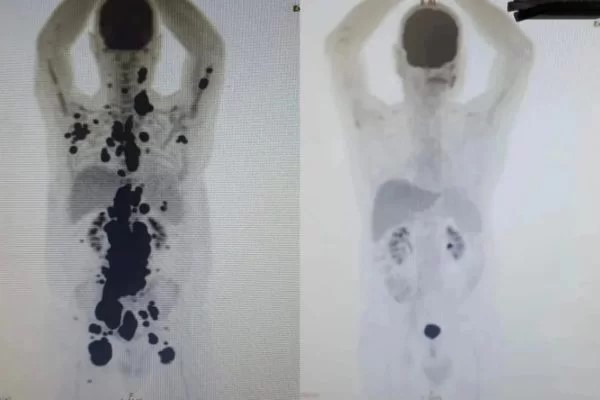

Uma nova terapia experimental contra o câncer, a terapia CAR-T, está atraindo atenção no Brasil após uma resposta notável em um paciente que lutava contra a doença há 13 anos. Paulo Peregrino, de 61 anos, testemunhou uma remissão completa de seu linfoma em apenas um mês de tratamento, algo antes inimaginável.

Peregrino, que viveu com linfoma nos últimos cinco anos e enfrentou outros tumores ao longo dos últimos 13 anos, estava à beira de ser transferido para cuidados paliativos quando foi escolhido para participar do estudo experimental da terapia celular CAR-T.

Peregrino foi um dos 14 pacientes escolhidos para testar o tratamento. Seu caso, com uma recuperação completa em apenas um mês, destacou-se, embora todos os pacientes do estudo tenham experimentado uma redução significativa de seus tumores, de pelo menos 60%.

O hematologista Vanderson Rocha, que supervisionou o caso de Peregrino, expressou sua emoção ao ver os resultados: "Por algumas vezes, tememos que ele não resistisse. Paulo lutou muitas batalhas. Só posso dizer que assim como ele também sou grato por estar vivendo para participar e assistir tudo isso acontecendo no Brasil."